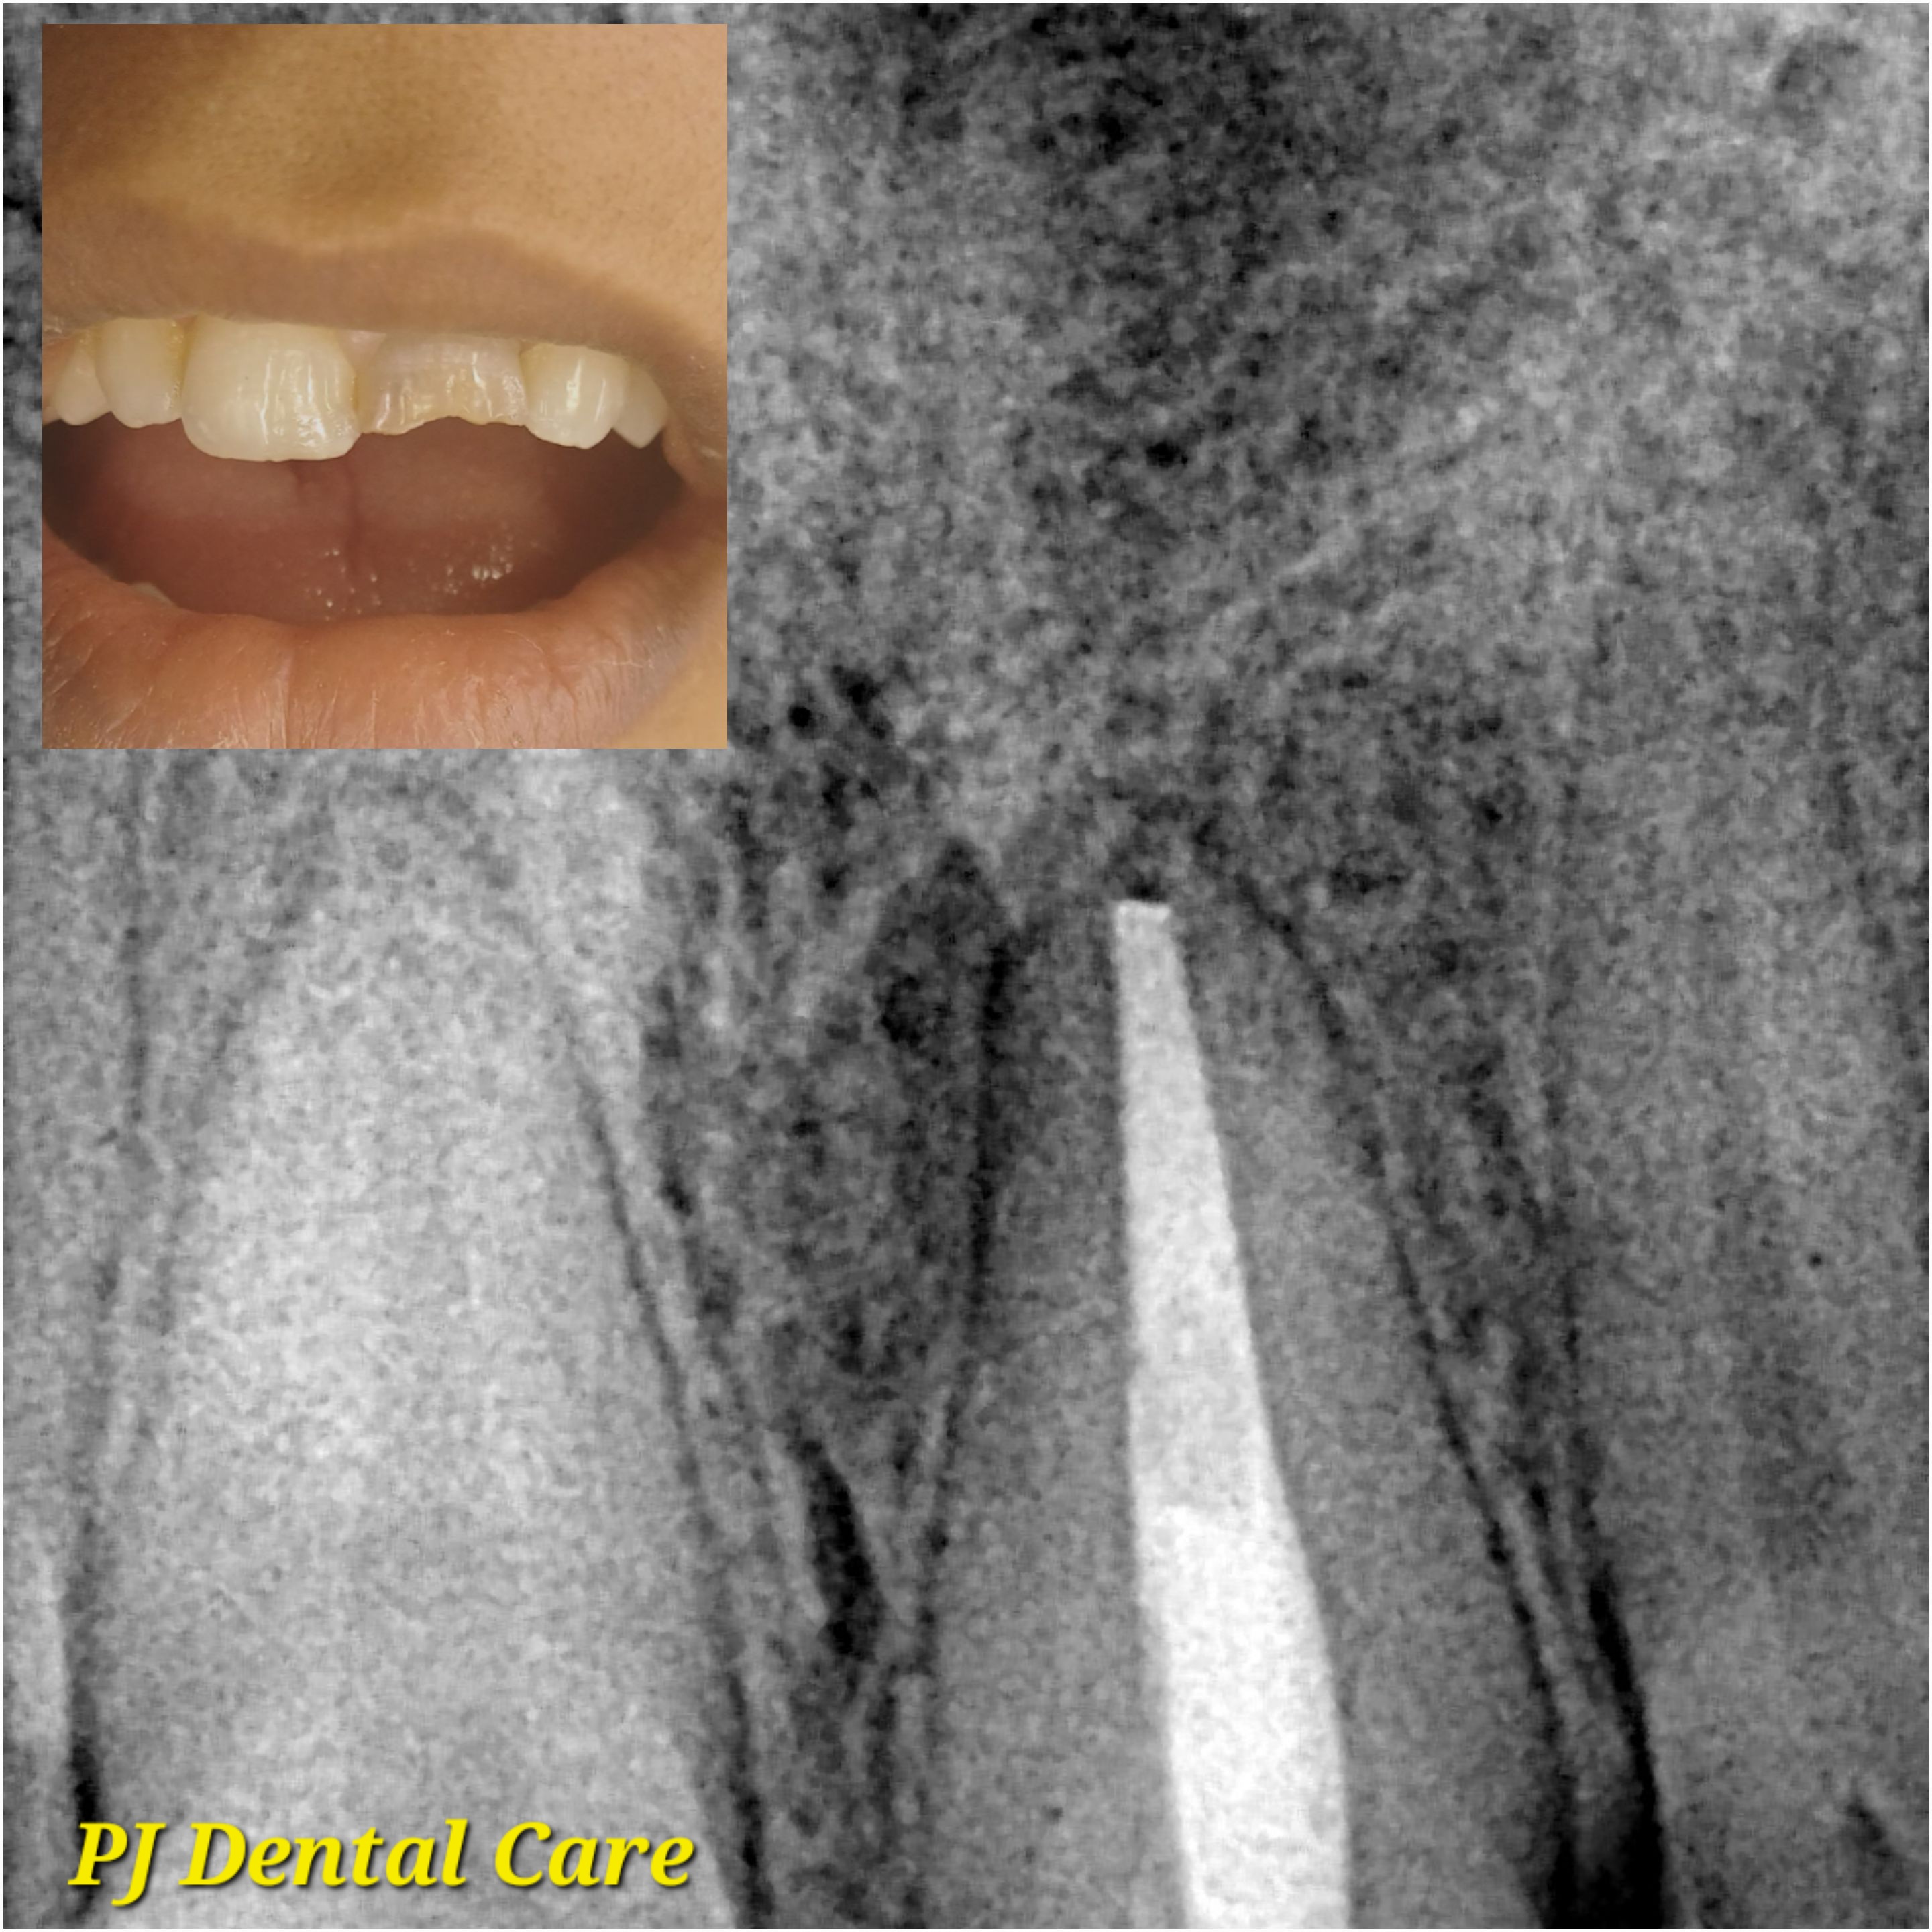

Your leading choice for dental, laser, and permanent makeup services in Tirupati. PJ Dental and Aest... hetics (Ph: 9148118616) offers affordable implants, root canals, laser hair reduction, lip blush, and more since 2012. We ensure the best treatment outcomes at reasonable prices. Read more